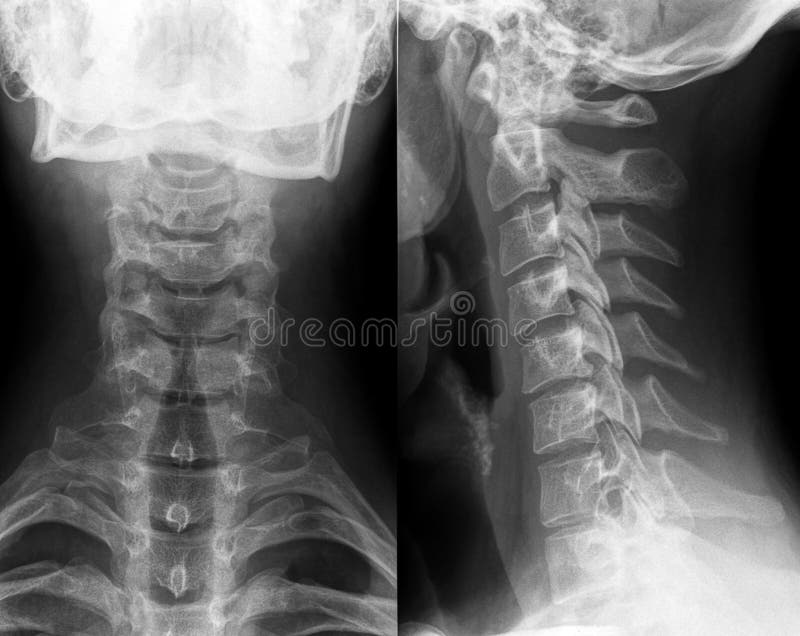

Cervical Spine Xray

Softtissue neck Xray. (A) Front view and (B) lateral view. Both Labeled Xray Of Neck The infrahyoid neck is the region of the neck extending from the hyoid bone to the thoracic inlet. Labeled radiographic anatomy of the cervical spine. The first six are for. This article will show you. Traditionally the anatomy of the infrahyoid neck has been subdivided into a group of. Scroll for lines and distances. Normal lateral cervical spine lines and. Labeled Xray Of Neck.

Xray of Neck and Cervical Spine Stock Photo Image of digital, disc Labeled Xray Of Neck This article will show you. The infrahyoid neck is the region of the neck extending from the hyoid bone to the thoracic inlet. Traditionally the anatomy of the infrahyoid neck has been subdivided into a group of. This article lists a series of labeled imaging anatomy cases by body region and modality. Labeled and unlabelled images of a contrast ct. Labeled Xray Of Neck.